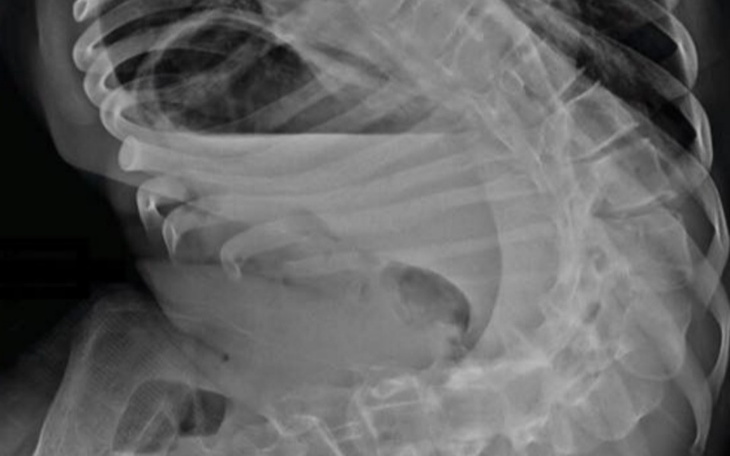

9 grudnia 2020 otrzymałam wynik badania - zmiany wytwórcze w stawach międzykręgowych. O ile 5-cio milimetrowe uwypuklenie krążka międzykręgowego nie uciska na korzenie nerwowe, o tyle przepuklina jądra miażdzystego (12 mm), daje mi się we znaki. Dosłownie.

I nadszedł dzień 29 marca 2021 - budzę się z niedowładem lewej strony, paraliżem... Udało mi się skontaktować z lekarzem, który podejmie się natychmiastowej operacji - 8 września 2021. Doktor wykona zabieg mikrodyscektomii. Koszt takiej operacji to 10.000 zł. Czekają mnie też badania przed zabiegiem oraz późniejsza rehabilitacja.